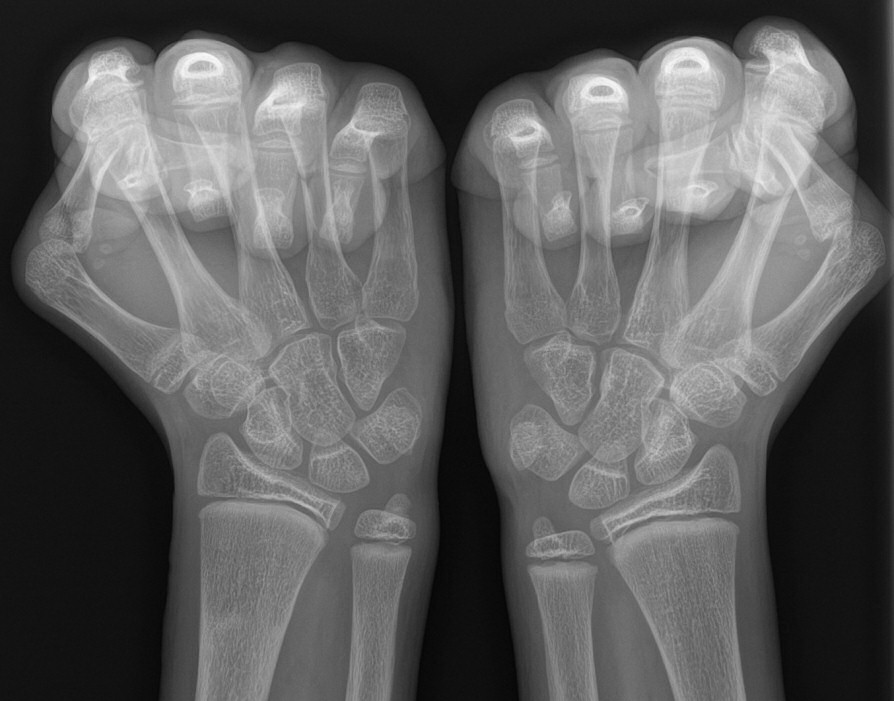

Provocerad röntgenbild som visar ökat avstånd mellan distala radius och ulna vänster hand hos ungdom.

Annars är ofta röntgenbilden normal, och krävs inte för diagnos av TFCC-skada.